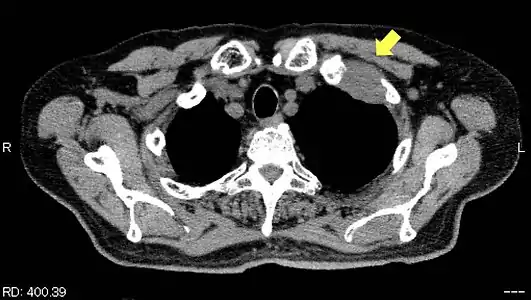

TDM d'une tumeur de Pancoast gauche envahissant l'arc antérieur de la 1re et de la 2e côte (flèche jaune).

PET-scanner du même patient[14].